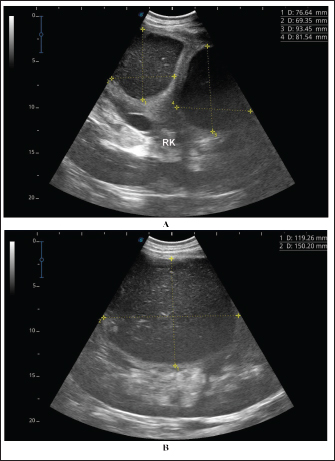

Fig. 4. Ultrasonographic findings of camel number 1 with abscessation of the right kidney. A large abscess was found in image A measuring 12.5 × 11.6 cm with hypoechoic contents and a thick capsule. The abscess in image B compresses the parenchyma of the right kidney (RK) and measuring 7.2 × 7.9 cm with echogenic contents and a thick capsule.

A detailed description of the renal abscesses is presented in Figures 410. Figure 4 shows sonographic findings in camel number 1 with abscessation of the right and left kidneys. A large abscess measuring 12.5 × 11.6 cm with hypoechoic contents and a thick capsule was detected. A second abscess in the same camel was imaged compressing the parenchyma of the right kidney and measuring 7.2 × 7.9 cm with echogenic contents and a thick capsule. Figure 5 shows ultrasonographic results in camel numbers 2 and 4 with right kidney abscesses. The lesions in camel number 2 appeared markedly large, compressing the renal parenchyma, with echogenic contents and a thickened capsule. The lesion in camel number 4 appeared to compress the renal parenchyma of the right kidney, measuring 6.7 × 8.2 cm with echogenic contents and a thick capsule. In addition, Figure 6. clarifies sonographic findings in camel number 6, where the abscess appeared within the right kidney. The contents were heterogeneous, but the capsule could not be imaged. The urinary bladder in the same animal was imaged with echogenic deposits that appeared highly echogenic compared with the echogenic urine.

Ultrasonographic findings in camel number 9 with right kidney abscesses are shown in Figure 7, where the lesion appeared compressing the parenchyma of the right kidney. Its contents are hyperechoic, and its capsule is thick. Figure 8 shows sonographic findings in camel number 11 with abscessation of the right and left kidneys. Abscesses measured 7.6 × 6.9 cm and 9.3 × 8.1 cm with isoechoic contents. A third abscess in the same camel was found within the left kidney. It was relatively large and was isoechoic. Ultrasonographic findings in camels 15 and 16 with abscesses of the left kidney are shown in Figure 9. A large abscess was found in camel number 15 with isoechoic contents and a thick capsule, while a small abscess was imaged in the left kidney of animal number 16 with heterogeneous contents. Figure 10 shows the ultrasonographic findings in camel number 17 with abscessation of the left kidney. A large abscess was found compressing the parenchyma of the left kidney with isoechoic contents. The urinary bladder in the same camel contained echogenic deposits that appeared to be highly echogenic.

Fig. 5. Ultrasonographic findings in camel numbers 2 (A) and 4 (B) with right kidney abscesses. The abscess in image A appeared markedly large and compresses the renal parenchyma with echogenic contents and a thickened capsule (stars). The lesion in image B is compressing the parenchyma of the right kidney (RK) and measuring 6.7 × 8.2 cm with echogenic contents and a thick capsule.